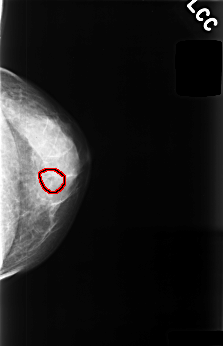

C_0477_1.LEFT_CC

LEFT_CC LINES 4488 PIXELS_PER_LINE 2896 BITS_PER_PIXEL 12 RESOLUTION 50 OVERLAY

FILE: C_0477_1.LEFT_CC.OVERLAY

TOTAL_ABNORMALITIES 1

ABNORMALITY 1

LESION_TYPE CALCIFICATION TYPE PUNCTATE DISTRIBUTION CLUSTERED

ASSESSMENT 4

SUBTLETY 3

PATHOLOGY BENIGN

TOTAL_OUTLINES 1

BOUNDARY